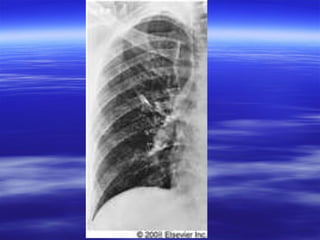

HHaammppttoonn’’ss hhuummpp

 DDoommee sshhaappeedd pplleeuurraall bbaasseedd ooppaacciittyy dduuee ttoo

lluunngg iinnffaarrccttiioonn..

 PPuullmmoonnaarryy iinnffaarrcctt iiss ddoommee sshhaappeedd iinnsstteeaadd

ooff bbeeiinngg wweeddggee sshhaappeedd bbeeccaauussee ooff ddoouubbllee

bblloooodd ssuuppppllyy wwiitthh pprreesseerrvveedd bbrroonncchhiiaall

aarrtteerriieess rreessuullttiinngg iinn ssppaarriinngg ooff tthhee eexxppeecctteedd

aappeexx ooff tthhee wweeddggee..

HHaammppttoonn’’ss hhuummpp DDoommee sshhaappeedd pplleeuurraall bbaasseedd ooppaacciittyy dduuee ttoo lluunngg iinnffaarrccttiioonn..  PPuullmmoonnaarryy iinnffaarrcctt iiss ddoommee sshhaappeedd iinnsstteeaadd ooff bbeeiinngg wweeddggee sshhaappeedd bbeeccaauussee ooff ddoouubbllee bblloooodd ssuuppppllyy wwiitthh pprreesseerrvveedd bbrroonncchhiiaall aarrtteerriieess rreessuullttiinngg iinn ssppaarriinngg ooff tthhee eexxppeecctteedd aappeexx ooff tthhee wweeddggee..